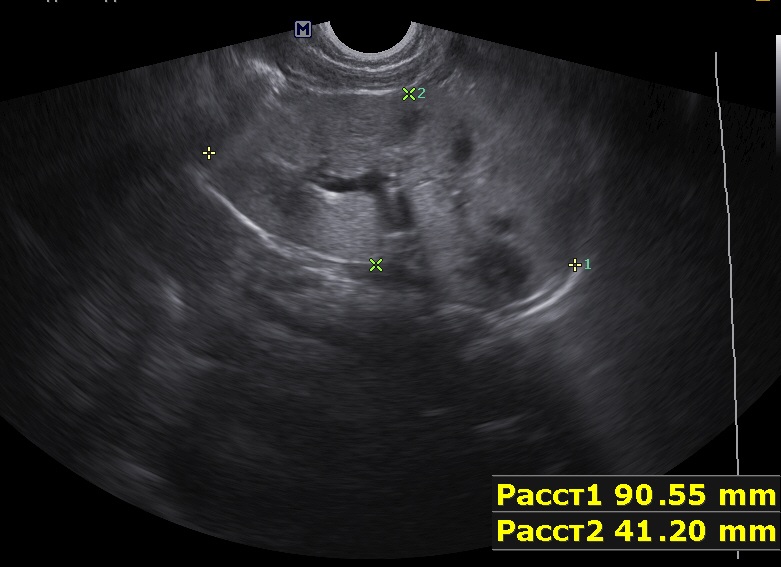

Ребенок 9мес, старшая сестра 9лет с ювенильным поликистозом (в н.в. ХБП 2).

Первые изменения в 1 мес, увеличение размеров почек.

Осмотрен мной ребенок впервые, обращено внимание на большие почки, 90х40мм, паренхима 17-18мм, корковый слой гиперэхогенный, пирамидки дифференцируются. Линейным датчиком определяется: кисты или расширенные канальцы в пирамидках. Структура печени в 1 мес была не изменена, в н.в. отмечается перипортальный фиброз, размеры печени и селезенки увеличены.

Поставил медуллярную кистозную дисплазию, почитав литературу предполагаю нефронофтиз Фанкони, но к сожалению не нашел картинки только описание данной болезни. Поделитесь своим мнением.

правая почка.jpg